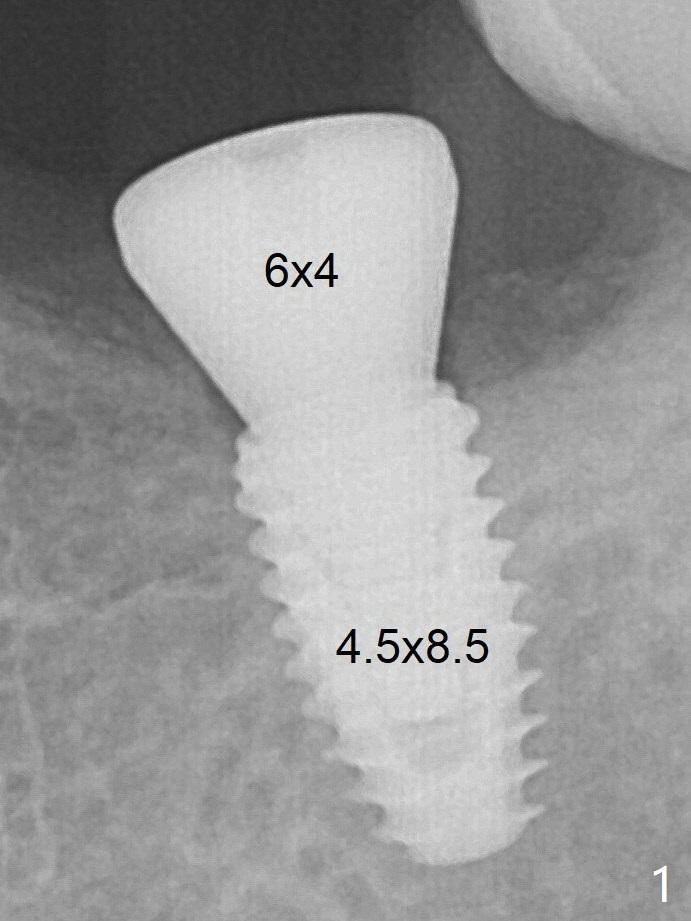

With 34 mg of Lidocaine and 17 mcg of Epinephrine (local infiltration), a 4.5x8.5 mm implant is placed with guide. The insertion torque is ~50 Ncm.  It is placed in precise depth and in a short period of time (tolerable to the operators and patient, easier than mini-implant placement, Fig.1).  Minimal bone resorption at the crest is noted nearly 4 months postop (Fig.3).  *: gingiva.